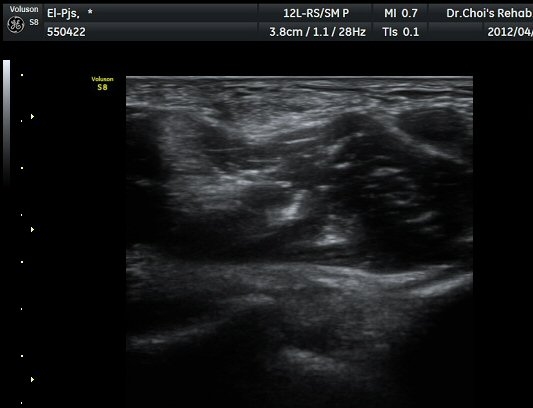

ŽÃËÀÚ¸¦ ÆÈ²ÞÄ¡ ¸»´ÜÀ¸·Î À̵¿ÇÏ´Ï À̵ιڱ٠ÈûÁÙÀÇ ºñÈÄ¿Í ÈûÁÙ ÁÖÀ§¿¡ Àú¿¡ÄÚ ¼ö¾×Àú·ù°¡ ]

°üÂûµÈ´Ù(±×¸² 2, 3, 4, 5). ŽÃËÀÚ¸¦ ¸»´ÜÀ¸·Î À̵¿ÇÒ ¶§ ŽÃËÀÚ¸¦ ¸Ó¸®ÂÊÀ¸·Î °æ»ç(tilting)½ÃÄѾß

À̵ιڱ٠ÈûÁÙ¿¡ Á÷°¢ ÀÇ ÃÊÀ½ÆÄ Á¶»ç°¡ °¡´ÉÇÏ¿© À̵ιڱ٠ÈûÁÙÀÌ °í¿¡ÄÚ·Î °üÂûµÈ´Ù.

À̵ιڱ٠ÈûÁÙ Á¾´Ü¸é°Ë»ç¿¡¼­ ÈûÁÙÀÇ ºñÈİ¡ °üÂûµÇ³ª ÈûÁÙÀÇ ¿ä°ñµ¹±â(radial tuberosity)

ºÎÂøºÎ´Â ºñµî¹æ¼ºÀΰøÀ½¿µ(anisotopic artifact) ¶§¹®¿¡ ¶Ñ·ÈÈ÷ °üÂûµÇÁö ¾Ê´Â´Ù(±×¸² 6).